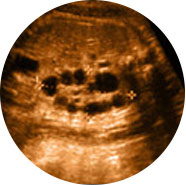

四维彩超能多方位、多角度、立体显示胎儿生长发育情况,为早期诊断胎儿先天性体表畸形如唇裂,脊柱裂,大脑、肾、心脏、骨骼发育不良等,和先天性心脏疾病提供全面的科学依据。

肾积水

时间是24-28周,因为这期间,胎儿中等大小,羊水较多,胎儿活动度大,有利于四维超声成像。

特别提醒一般而言孕期可分为三个阶段:孕前期 (14周之前),孕中期(14-27周),孕晚期(28周之后),这三个时期做出来的四维彩超效果就会不同。